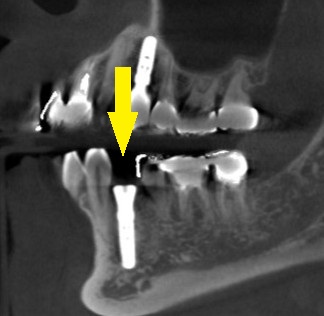

下の写真が、手術前後のCTです。